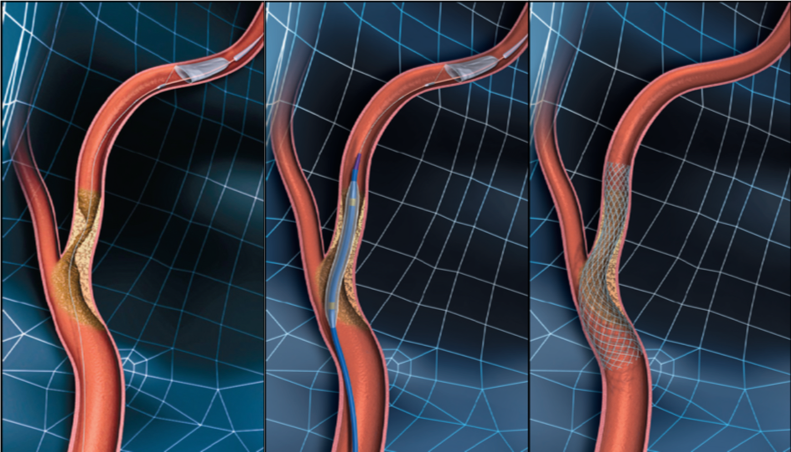

頚動脈ステント留置術

局所麻酔で手術を行います。足の付け根の動脈(大腿動脈)からカテーテルを挿入し,フィルターあるいはバルーン等で術中に血栓などが飛ばないように保護しながら(図4)、バルーンカテーテルで狭窄部を広げ(図5)ステントを留置(図6)し,血流の改善をはかります。当院では積極的に頚動脈ステント留置術を第一選択として治療を行っております。

図4-6 頚動脈ステント留置術のイラスト図です。